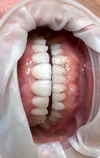

Ortodonti, estetik diş hekimliği, implantoloji ve pedodonti dallarında yoğunlukla çalışmaktayım aynı zamanda "Dişlerim ve Ben" adlı çocuk kitabını yazdım.

Uzmanlık alanları

Diş hekimi